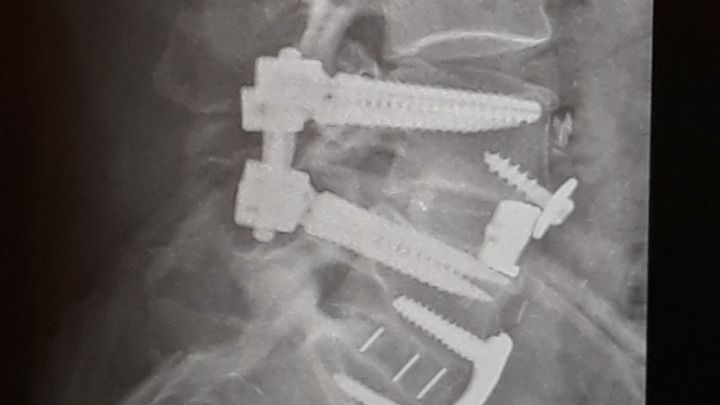

Nerves in my spine were damaged during back surgery causing pain down legs into feet, numbing feet, and chronic lower back pain with constant spasms.